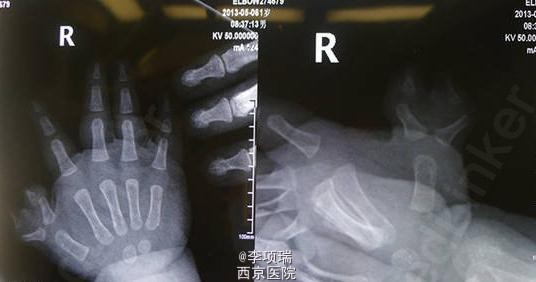

蟹钳指传统BC融合术

患儿,男,1岁2月,蟹钳指,侧弯严重,采用传统BC融合术。术后1个半月,家长述手指已经完全伸直,MP活动可,IP主动活动轻微,被动活动可以正常。